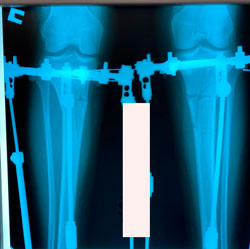

перед крутками

image-25-12-20-11-54.jpg